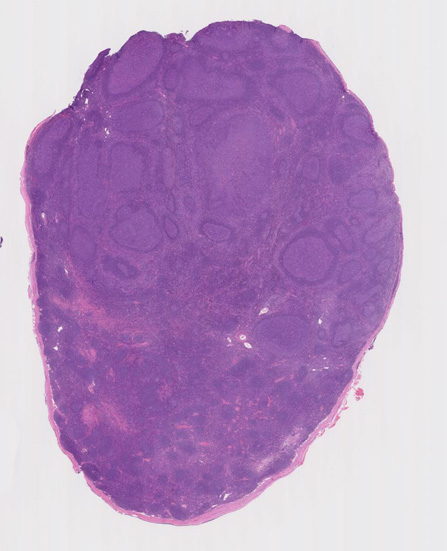

43歳男性 頸部リンパ節

平成X年1月頃から頸部他表在リンパ節の腫大あり。精査を行うが悪性疾患の可能性乏しく経過観察となる。11月になっても頸部リンパ節の腫大が改善せず。生検をおこなう。 軽度肝機能障害ありAST 61, ALT 132, LDH 175IU/l, sIL-2R 422, CRP(-)

大きな胚中心を持つ多数のリンパ濾胞が見られる。胚中心の辺縁は不明瞭でマントル層も薄くなっている。1カ所マントル層リンパ球の侵入によりバラバラになった巨大な胚中心が認められ, macrofollicular patternと記載されるPTGCです。

鑑別にあがるfollicular lymphoma floral variantは全ての濾胞が腫瘍性であり, 本性例では除外可能と考える。

Diagnosis: Reactive lymphadenitis with PTGC